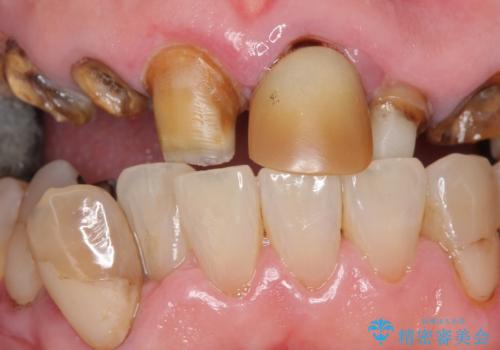

- 前歯の被せ物がとれたまま放置されていた患者様です。

前歯4本のうち3本の被せ物が脱離し、残りの1本の被せ物は劣化し変色していました。

古い被せ物や土台・虫歯をしっかり除去したのち、セラミック治療を行いました。